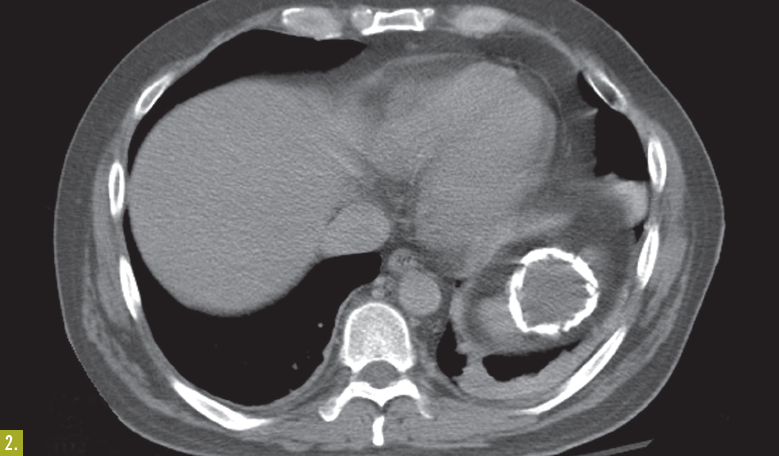

A 38-year-old man found lying on the floor in his home was hospitalized because of alcohol intoxication. A chest radiograph showed a large calcified lesion in the left upper abdomen (Figure 1). A CT scan with intravenous contrast revealed a large, well-defined, cystic mass with mural calcification in the spleen (Figure 2)

The CT findings were not consistent with a vascular malformation or echinococcal cyst—specifically, the mass was sharply demarcated, unilocular without septations, and round with a thin wall and attenuation similar to water. Urine Histoplasma antigen test results were negative.

Laboratory testing. The patient underwent CT-guided aspiration of the cyst, and the fluid was cultured and examined under microscopy. Culture, cytology, and Gram stain results were negative, and no parasitic elements were identified under microscopy. Based on these results and the lack of a patient history of pancreatitis, traumatic calcified splenic cyst was diagnosed.